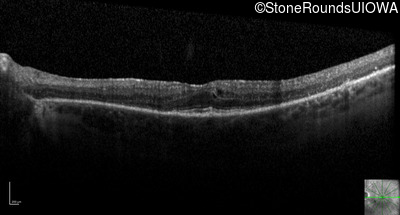

Optical Coherence Tomography - Right - 20/50 +1

Exemplar / OCT Stack